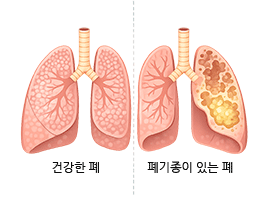

폐기종 (Emphysema)